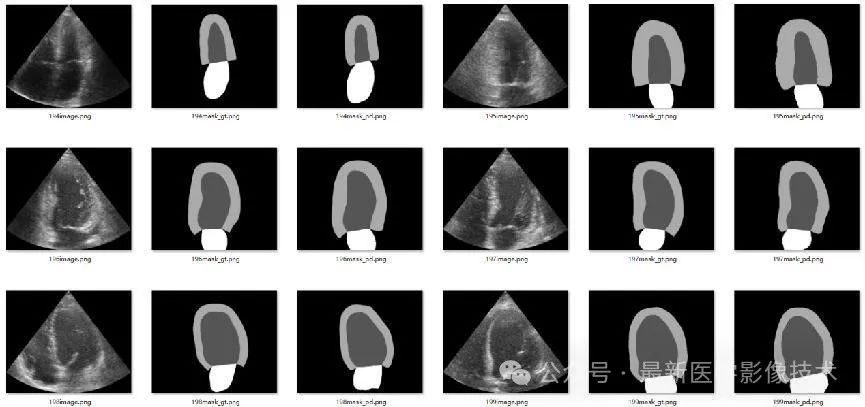

4、验证集部分分割结果